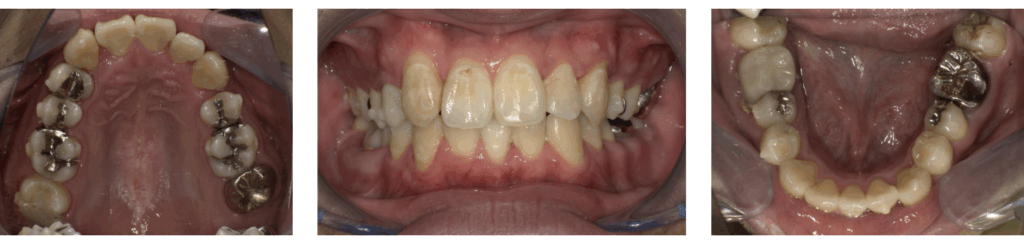

ここでは、当院でマウスピースを用いた矯正治療を行った症例をご紹介します。仕事を続けながら、目立たない装置で自然な口元を目指したケースです。

| 周囲の反応 | 矯正治療前は自分の子供に「パパ、変な歯が生えてるー!」とバカにされていたが、きれいに歯が並んでびっくりしていた。 |

| 治療方法 | マウスピース矯正(インビザライン) |

| 治療期間 | 2年1か月 |

| 費用 | 88万円 |

| 年齢特有の対応 | ガタガタがかなり重度だったため、上下で合計3本の歯を抜歯する効率を考えた矯正治療プランを立てた。 |

治療後